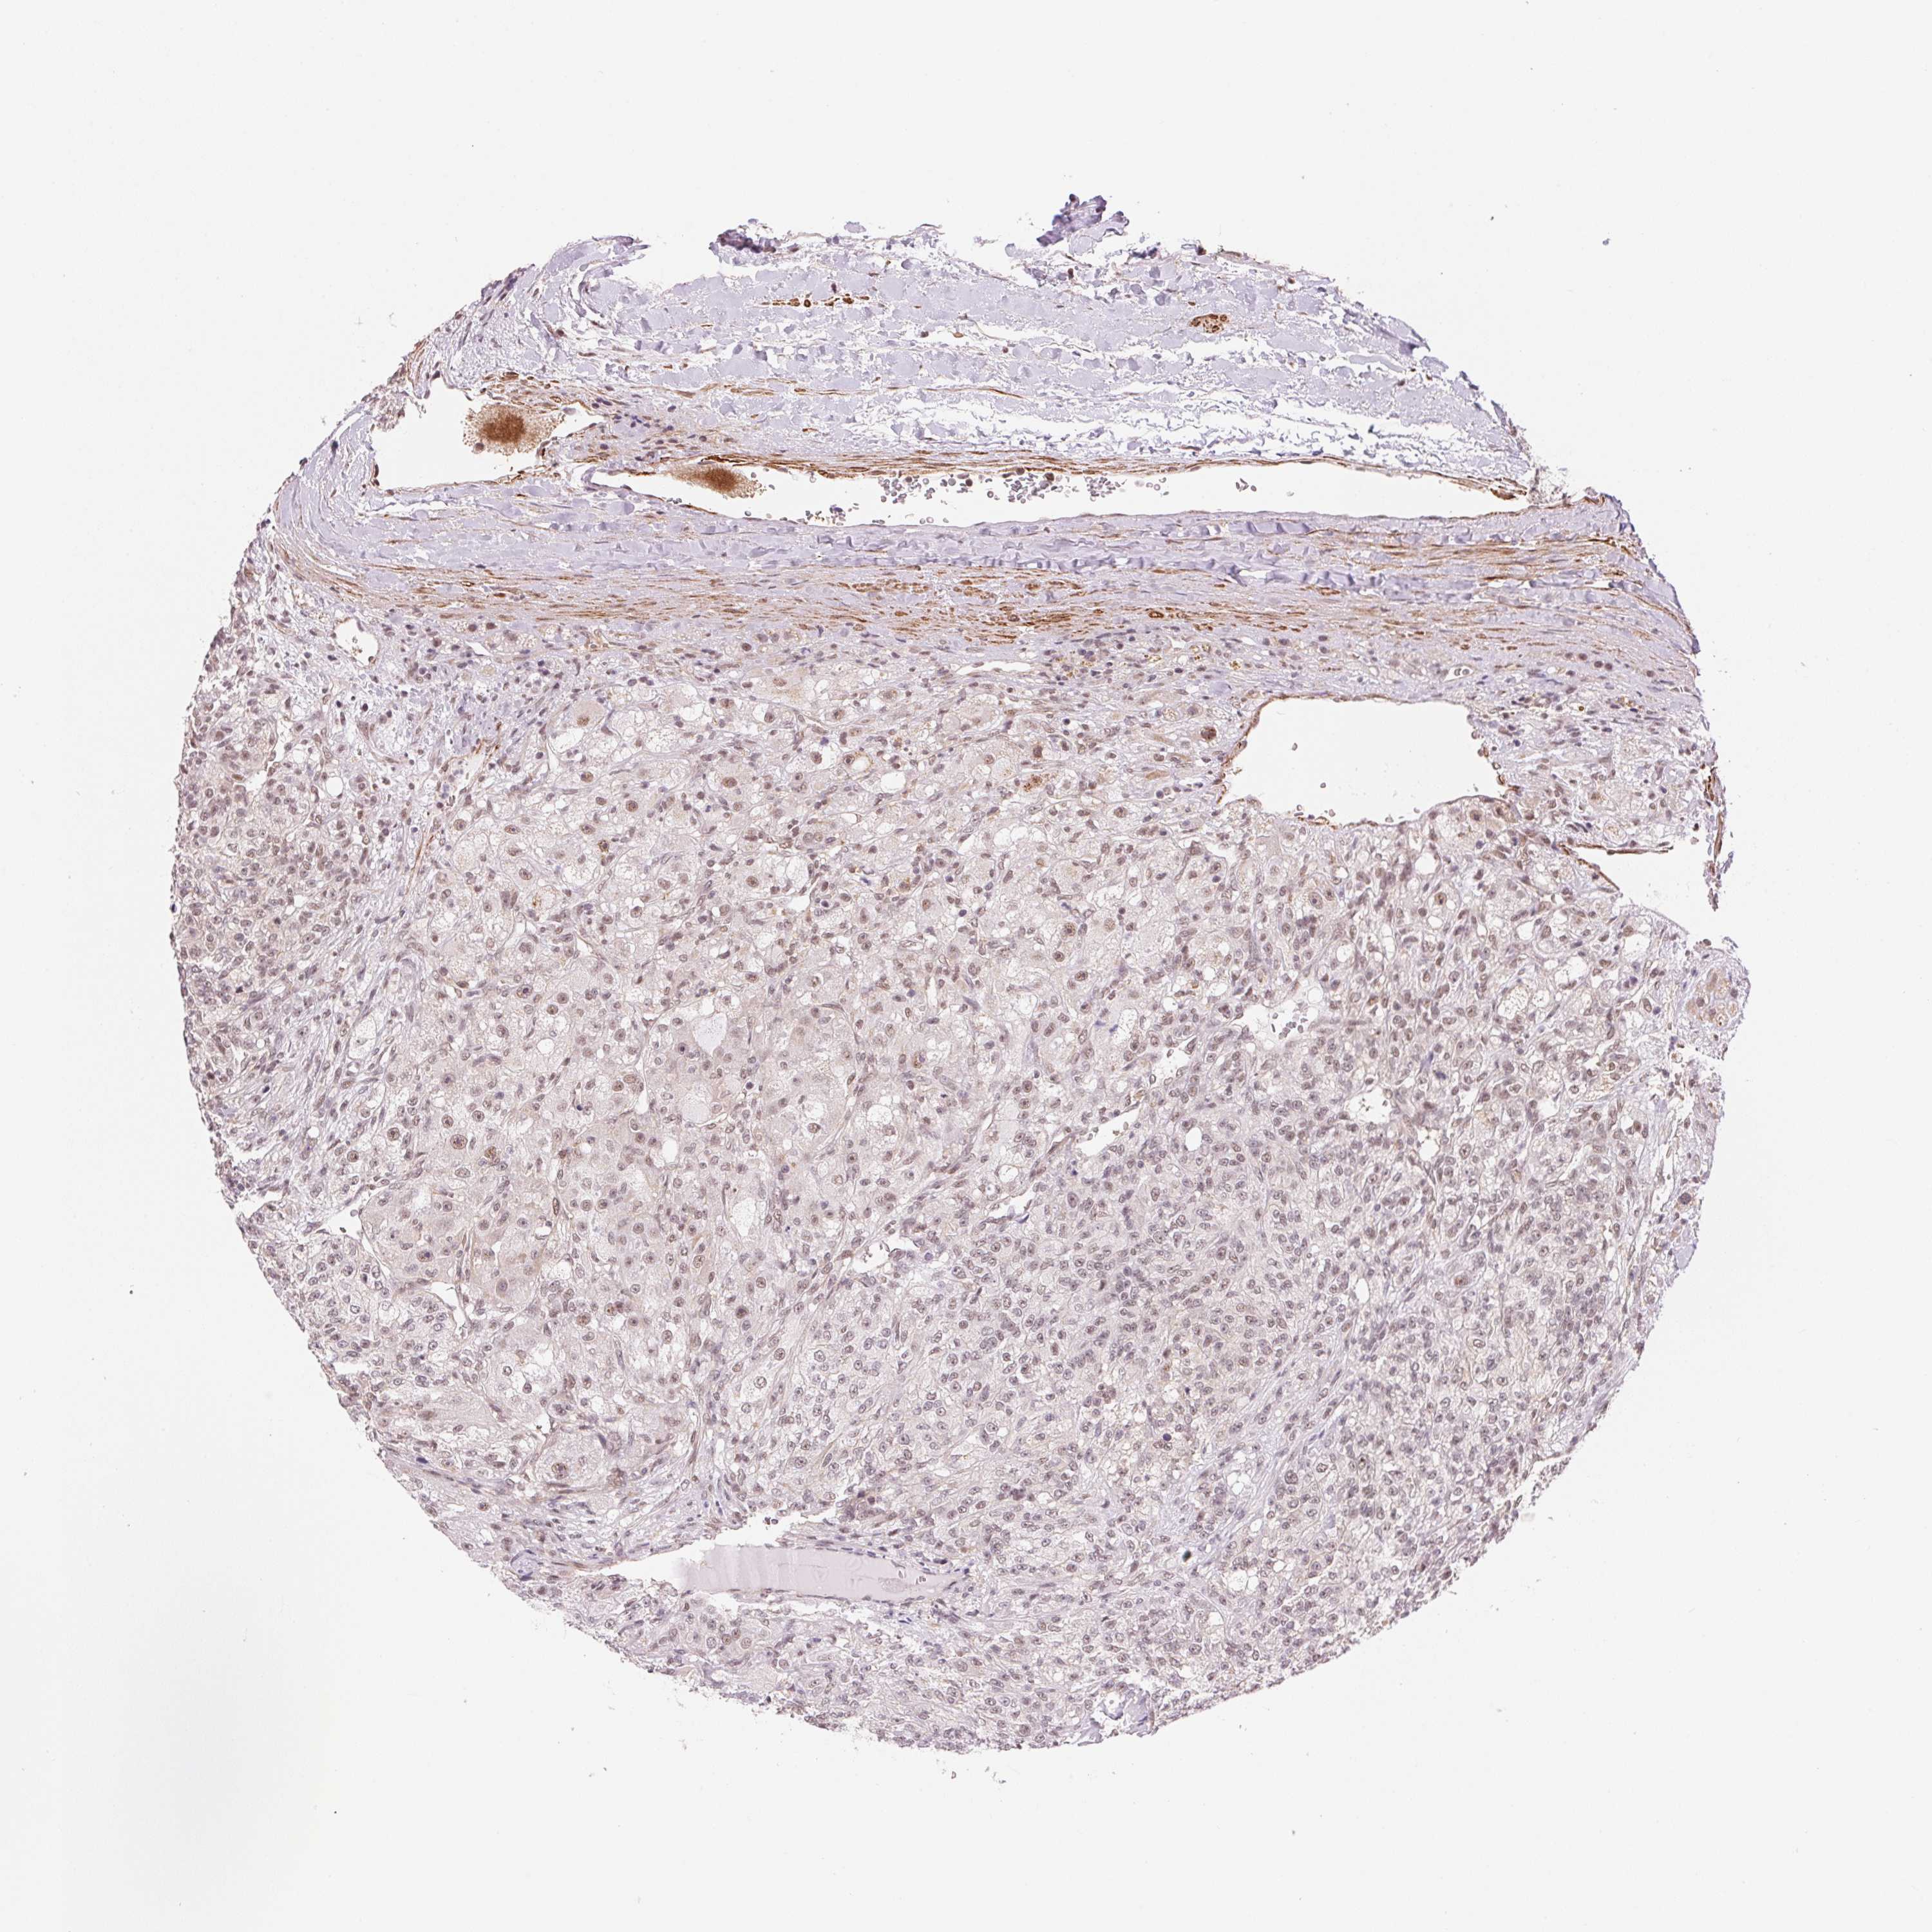

KIDNEY RENAL CLEAR CELL CARCINOMA (VALIDATION) - Interactive survival scatter ploti

The Survival Scatter plot shows the clinical status (i.e. dead or alive) for all individuals in the patient cohort, based on the same data that underlies the corresponding Kaplan-Meier plots. Patients that are alive at last time for follow-up are shown in blue and patients who have died during the study are shown in red.

The x-axis shows the expression levels (FPKM) of the investigated gene in the tumor tissue at the time of diagnosis. The y-axis shows the follow-up time after diagnosis (years). Both axes are complimented with kernel density curves demonstrating the data density over the axes. The top density plot shows the expression levels (FPKM) distribution among dead (red) and alive patients (blue). The right density plot shows the data density of the survived years of dead patients with high and low expression levels respectively, stratified using the cutoff indicated by the vertical dashed line through the Survival Scatter plot. This cutoff is automatically defined based on the FPKM cutoff that minimizes the p-score. The cutoff can be changed by dragging the vertical line or by entering a cutoff value in the square labeled "Current cut-off".

Under the Survival Scatter plot the p-score landscape (black curve; left axis) is shown together with dead median separation (red curve; right axis). Dead median separation is the difference in median mRNA expression between patients who have died with high and low expression, respectively. It is calculated as follows: median FPKM expression of dead patients with high expression - median FPKM expression of dead patients with low expression. This is intended to aid the user in visually exploring custom cutoffs and the associated p-scores and dead median separation.

Individual patient data is displayed and can be filtered by clicking on one or more of the category buttons on the top of the page. Categories describing expression level and patient information include: high, low, alive, dead, female, male and tumor stages. The scale of the x-axis can be toggled between linear and log-scale by clicking on the "x log" button. Mouse-over function shows TCGA ID, patient information and mRNA expression (FPKM) for each patient.

& Survival analysisi

Kaplan-Meier plots summarize results from analysis of correlation between mRNA expression level and patient survival. Patients were divided based on level of expression into one of the two groups "low" (under cut off) or "high" (over cut off). X-axis shows time for survival (years) and y-axis shows the probability of survival, where 1.0 corresponds to 100 percent.

HNRNPDL is not prognostic in Kidney Renal Clear Cell Carcinoma (validation)

: 236.33

Average pTPM 209.4

Number of samples 100